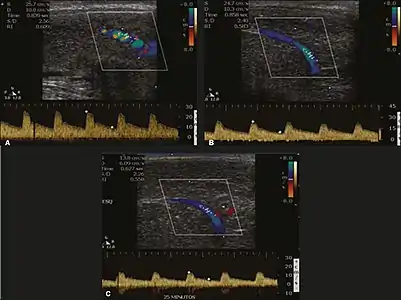

Erection can be induced by injecting 10–20 µg of prostaglandin E1, with evaluations of the arterial flow every five minutes for 25–30 min (see image). The use of prostaglandin E1 is contraindicated in patients with predisposition to priapism (e.g., those with sickle cell anemia), anatomical deformity of the penis, or penile implants. Phentolamine (2 mg) is often added. Visual and tactile stimulation produces better results. Some authors recommend the use of sildenafil by mouth to replace the injectable drugs in cases of contraindications, although the efficacy of such medication is controversial.[45]

Before the injection of the chosen drug, the flow pattern is monophasic, with low systolic velocities and an absence of diastolic flow. After injection, systolic and diastolic peak velocities should increase, decreasing progressively with vein occlusion and becoming negative when the penis becomes rigid (see image below). The reference values vary across studies, ranging from > 25 cm/s to > 35 cm/s. Values above 35 cm/s indicate the absence of arterial disease, values below 25 cm/s indicate arterial insufficiency, and values of 25–35 cm/s are indeterminate because they are less specific (see image below). The data obtained should be correlated with the degree of erection observed. If the peak systolic velocities are normal, the final diastolic velocities should be evaluated, those above 5 cm/s being associated with venogenic ED.[45]